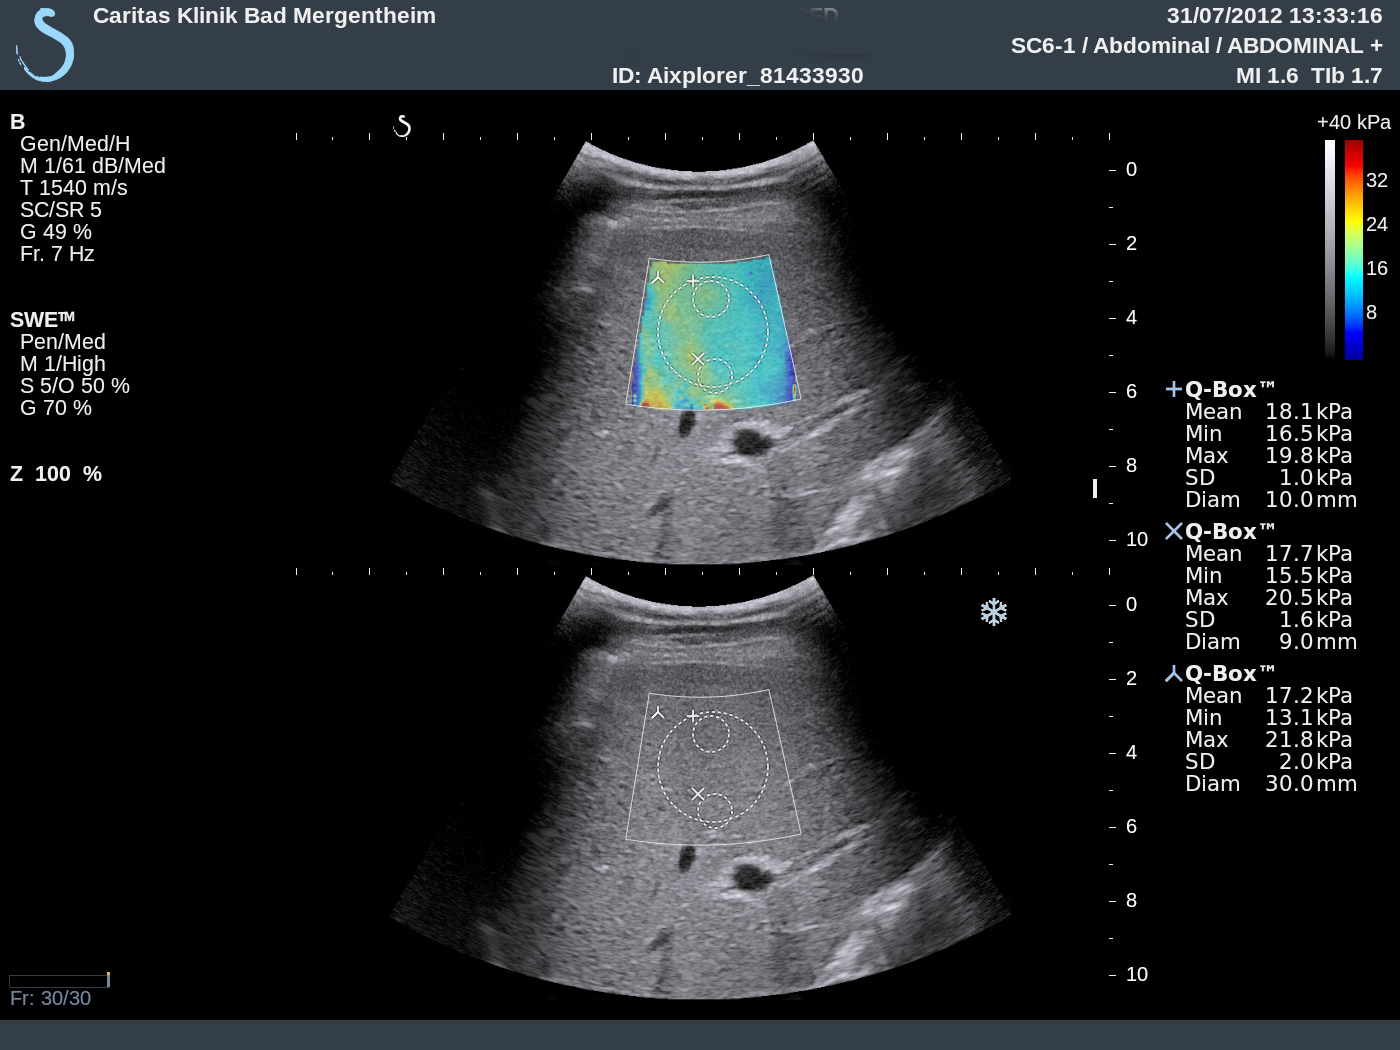

1 Case report We report on shear wave elastography using Supersonic Imaging (SSI) from a practical point. The procedure was repeated three times of three different scanning views in order to acquire three valid independent SWE™ maps. Examples are shown in Figure 1. The case reports in healthy subjects, patients with intermediate fibrosis and liver cirrhosis were summarized and analyzed to discuss basic principles, imaging acquisition, data reproducibility, advantages and limitations of this method as part of the Shear Wave Elastography Research Group activities (SWERG).

3.2.6 SWE™ stiffness quantification

Once the SWE™ map is satisfactory, freeze and select the Q-Box™ measurement tool. Resize its diameter to 15-20 mm if needed, place it preferably at the center of the SWE Box, over an area of relative homogeneous elasticity, at a depth of 3-5 cm; do not place it over an area with missing SWE™ pixels. On recent software versions of Aixplorer® liver package, a Stability Index has been added as an indicator of SWE map homogeneity and temporal stability. This index is displayed while positioning the built-in Q-Box™ quantification tool. A Stability Index below 90% should lead to the rejection of the Q Box™ location, and push the operator to find a better location. In the event no satisfactory location can be found on a given frozen SWE™ map, a new SWE™ acquisition should be performed.